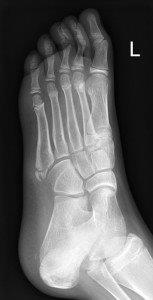

Avulsion fracture of base of fifth metatarsal

- Follow up Orthopaedic Fracture clinic 7- 10 days.

- If 4th and 5th inter-metatarsal joint involved (Jones Fracture), not suitable for CAM Boot.